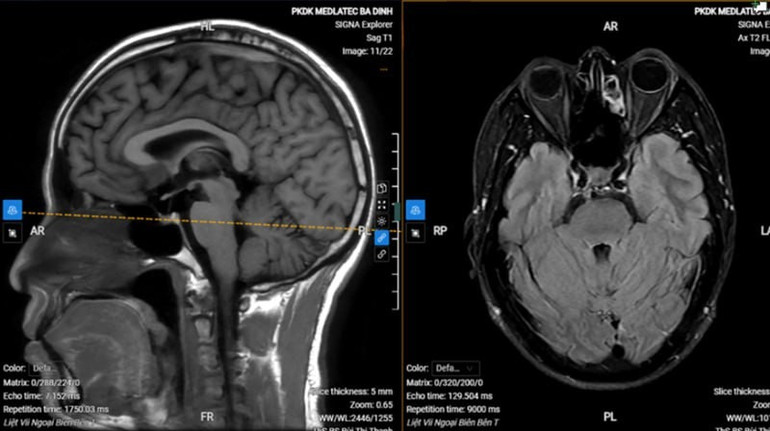

Chụp MRI sọ não cho thấy hình ảnh thoái hóa myelin chất trắng dưới vỏ bán cầu đại não bên hai bên (phân loại Fazekas độ 1), không thấy tổn thương cấp tính nội sọ.

Với kết quả trên, anh S. được chẩn đoán liệt dây thần kinh số VII ngoại biên trái vô căn (liệt Bell). Bệnh nhân được kê đơn điều trị ngoại trú, hướng dẫn tập các bài tập cơ vùng mặt, chăm sóc mắt, phối hợp châm cứu sau 1 tuần.

![]() |

| Hình ảnh chụp MRI của bệnh nhân. |